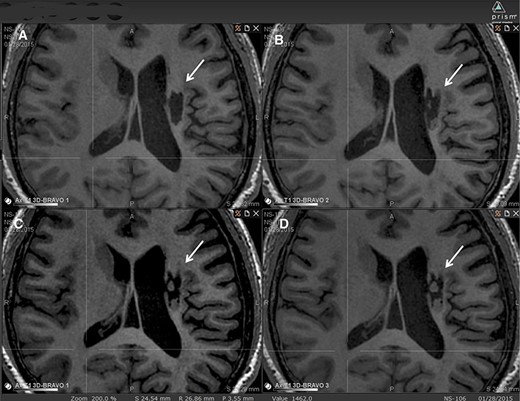

圖中顯示了B組 (#106) 受試者在T1MRI上隨時間的變化。

(A):基線時,(B) 6個月隨訪時,(C) 12個月隨訪時,(D) 24個月隨訪時。箭頭表示梗塞腔。

可以看到兩個組織團塊,在基線時不存在,推測是來自植入的NSI-566,隨著時間的推移,它們似乎慢慢填滿了腔體。